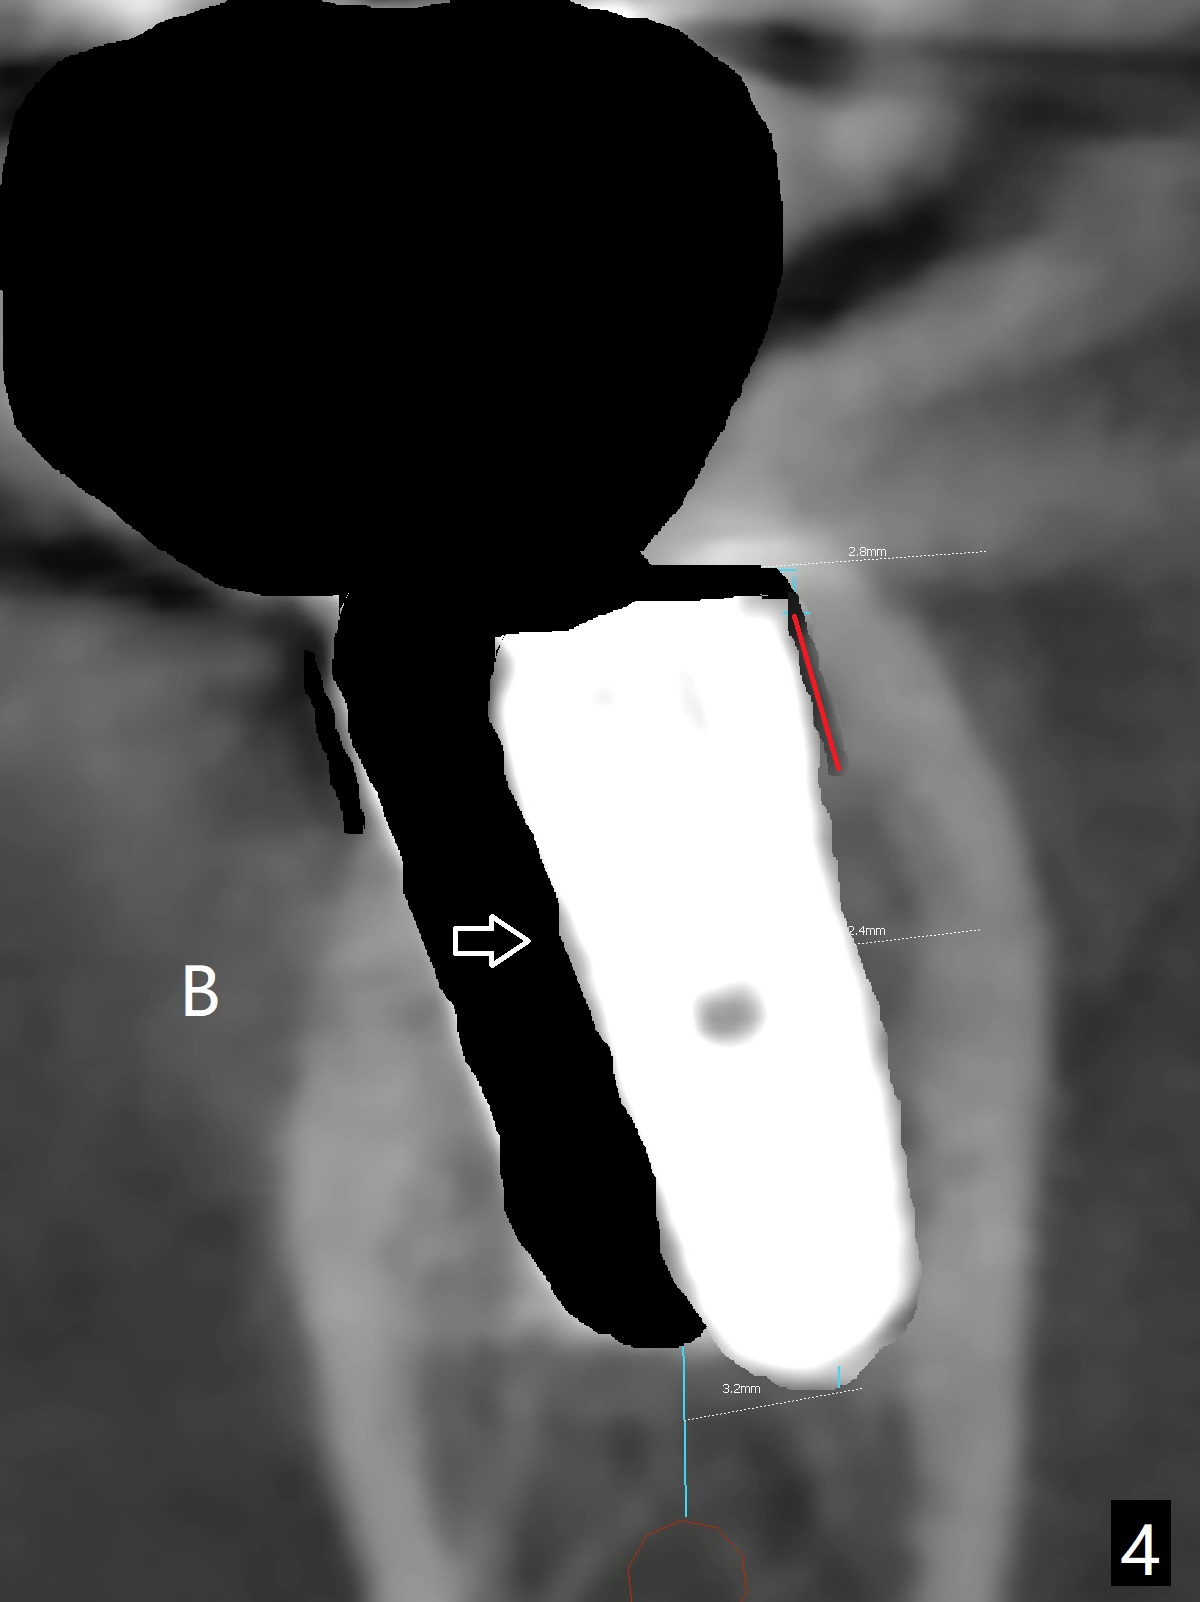

Twenty six months post cementation, periimplantitis develops buccally at #30 (Fig.1) due to buccal (B) placement (Fig.2) with buccal thread exposure (red line), as compared to the same sized implant at #19 (Fig.3). After removal of the crown and abutment and incision, use Titanium brush to clean the exposed threads. Following implant removal and removal of the lingual bone, place the same implant lingually (Fig.4 arrow) with the used-to-be-exposed surface facing lingual (Fig.4 red line). The buccal gap will be filled with autogenous bone harvested lingually and allograft. Use 2-3 pieces of PRF membranes to close the wound, i.e., to bury the implant. A 5x13 mm implant (Fig.5) placed lingually (Fig.6 L) appears to be unable to gain more than .77 mm native bone (Fig.7). Lab declines to make a guide.